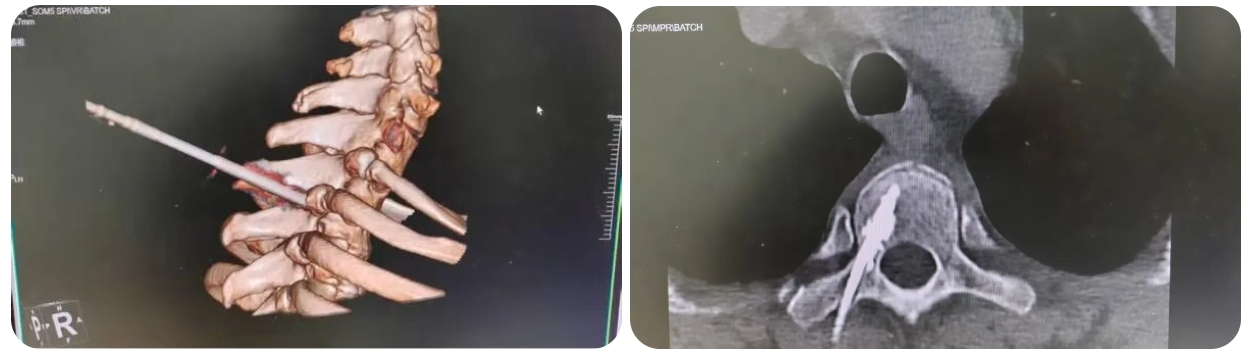

CT如同为医生装上了“透视眼”,能够实时、立体地显示穿刺针与周围组织的关系,有效避开骨骼遮挡与神经血管,实现毫米级精准定位。手术中,谢彪主任凭借丰富经验,以极细穿刺针精准进入病变椎体,顺利完成骨水泥注入。整个过程仅耗时30分钟,患者体表仅留下两个微小针眼。

(▲CT影像)